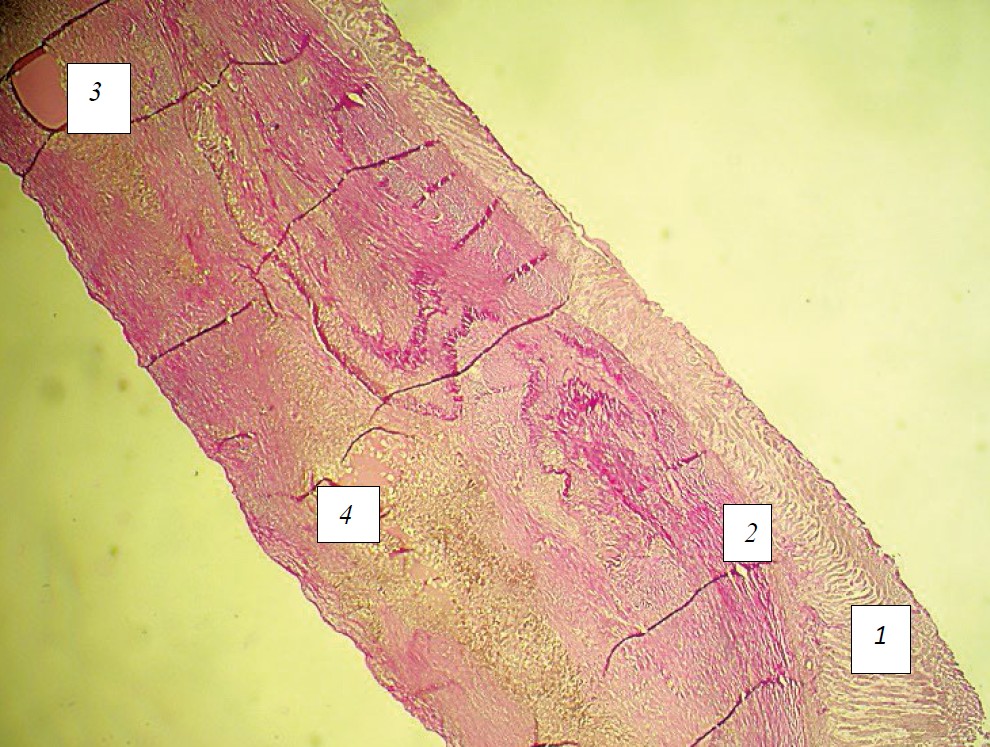

На 30‑е сутки на фоне сохранения анатомической непрерывности оболочек в группе 1 определяли истончение слизистой оболочки, выраженный склероз в подслизистой основе, а также в мышечной оболочке. При этом в мышечной оболочке рубцовая ткань заполняла область бывшего диастаза (рис. 8).

Рис. 8. Микроморфологическая картина стенки желудка кролика из группы № 1 (латексный тканевый композит) на 30 сутки эксперимента: 1 — слизистая оболочка: 2 — подслизистая основа; 3 — мышечная ткань; 4 — область нахождения нити; стрелкой указан диастаз. Ван-Гизон, ґ32

Источник: выполнено К.Т. Инапшба, М.Д. Качалиным, Е.Н. Борхуновой, Н.В. Кислиновской.

Fig. 8. Micromorphological picture of the stomach wall of a rabbit from group No. 1 (latex tissue composite) on the 30th day of the experiment: 1 — mucous membrane; 2 — submucosa; 3 — muscle tissue; 4 — area of thread location; diastasis is indicated by an arrow. Van Gieson, ґ32

Source: complied by K.T. Inapshba, M.D. Kachalin, E.N. Borkhunova, N.V. Kislinovskaya.

Во 2‑й экспериментальной группе слизистая оболочка отличалась большей толщиной, чем в группе 1, явление склероза в подслизистой основе были выражены в меньшей степени, а восстановление мышечной оболочки происходило главным образом за счет гладкой мышечной ткани (рис. 9). Это свидетельствует о лучшем восстановлении структуры стенки желудка после наложения шва и применения желатин-резорцинового клеевого композита в данной группе.

Рис. 9. Микроморфологическая картина стенки желудка кролика из группы 2 (желатино-резорциновый клей) на 30‑е сутки эксперимента: 1 — слизистая оболочка; 2 — подслизистая основа; 3 — мышечная ткань; 4 — область нахождения нити. Ван-Гизон, ґ32

Fig. 9. Micromorphological structure of the stomach wall of a rabbit from Group 2 (gelatin-resorcinol adhesive) on day 30 of the experiment. 1 — mucosa; 2 — submucosa; 3 — muscle tissue; 4 — thread location. Van Gieson stain, ×32